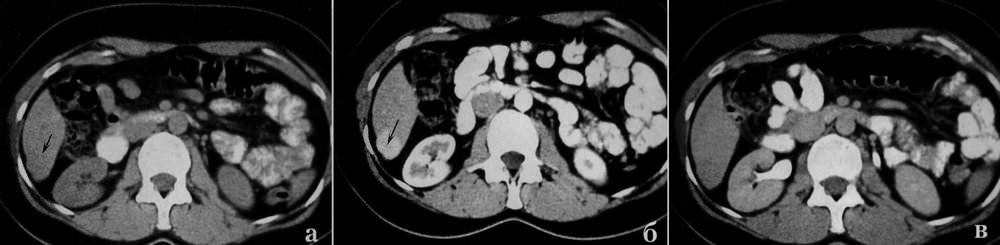

Узловая гиперплазия печени При нативном КТ исследовании (а) в 6 сегменте неотчетливо определяется образование, изоинтенсивное с паренхимой печени (стрелка). В артериальную фазу (б) контрастного усиления образование интенсивно и равномерно набирает контрастное вещество. В центе образования намечается формирование центрального рубца (стрелка). В венозную фазу (в) наблюдается вымывание контрастного вещества до состояния изоинтенсивности.

На не усиленных компьютерных томограммах узловая гиперплазия отображается по отношению к паренхиме печени или ограниченным слабо гиподенсивным, или же изоденсивным участком. В последнем случае выявление подобных образований на компьютерных томограммах проблематично. Однако эти образования в артериальную фазу контрастного усиления относительно равномерно и интенсивно окрашиваются вследствие их гиперваскуляризации и наличия соустий между артериальными и венозными сосудами (фото КТ выше). В венозную фазу окрашивание быстро убывает до состояния изоинтенсивности. Часто в центре образования на не усиленных компьютерных томограммах определяется зона более низкой плотности, которая в артериальную фазу контрастного усиления не накапливает контрастное вещество, а в поздней паренхиматозной фазе, через 4-5 минут после болюсного введения, интенсивно окрашивается. Эта зона соответствует центральному рубцу. Центральный рубец состоит из молодой, богато васкуляризированной соединительной ткани и лучше проявляется в образованиях большого размера — более 4 см (фото КТ ниже).